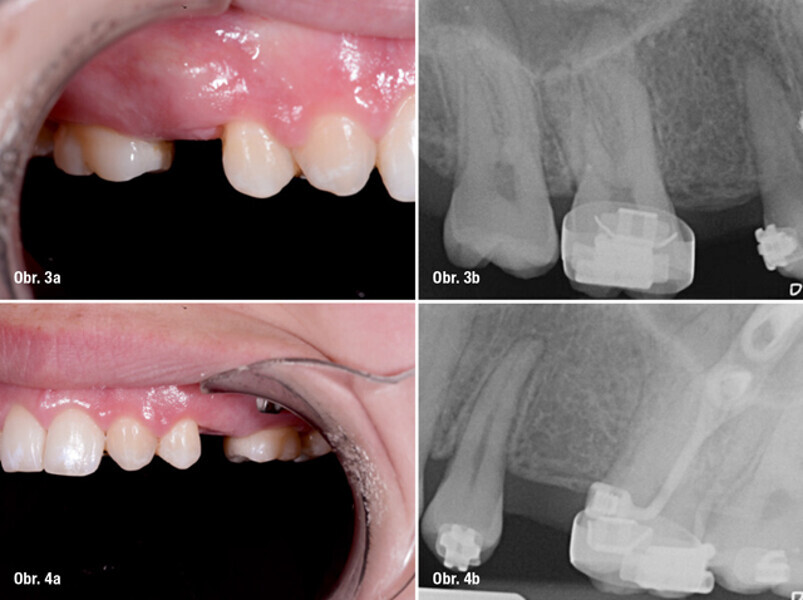

Implantace pomocí dynamické navigace s okamžitým zatížením